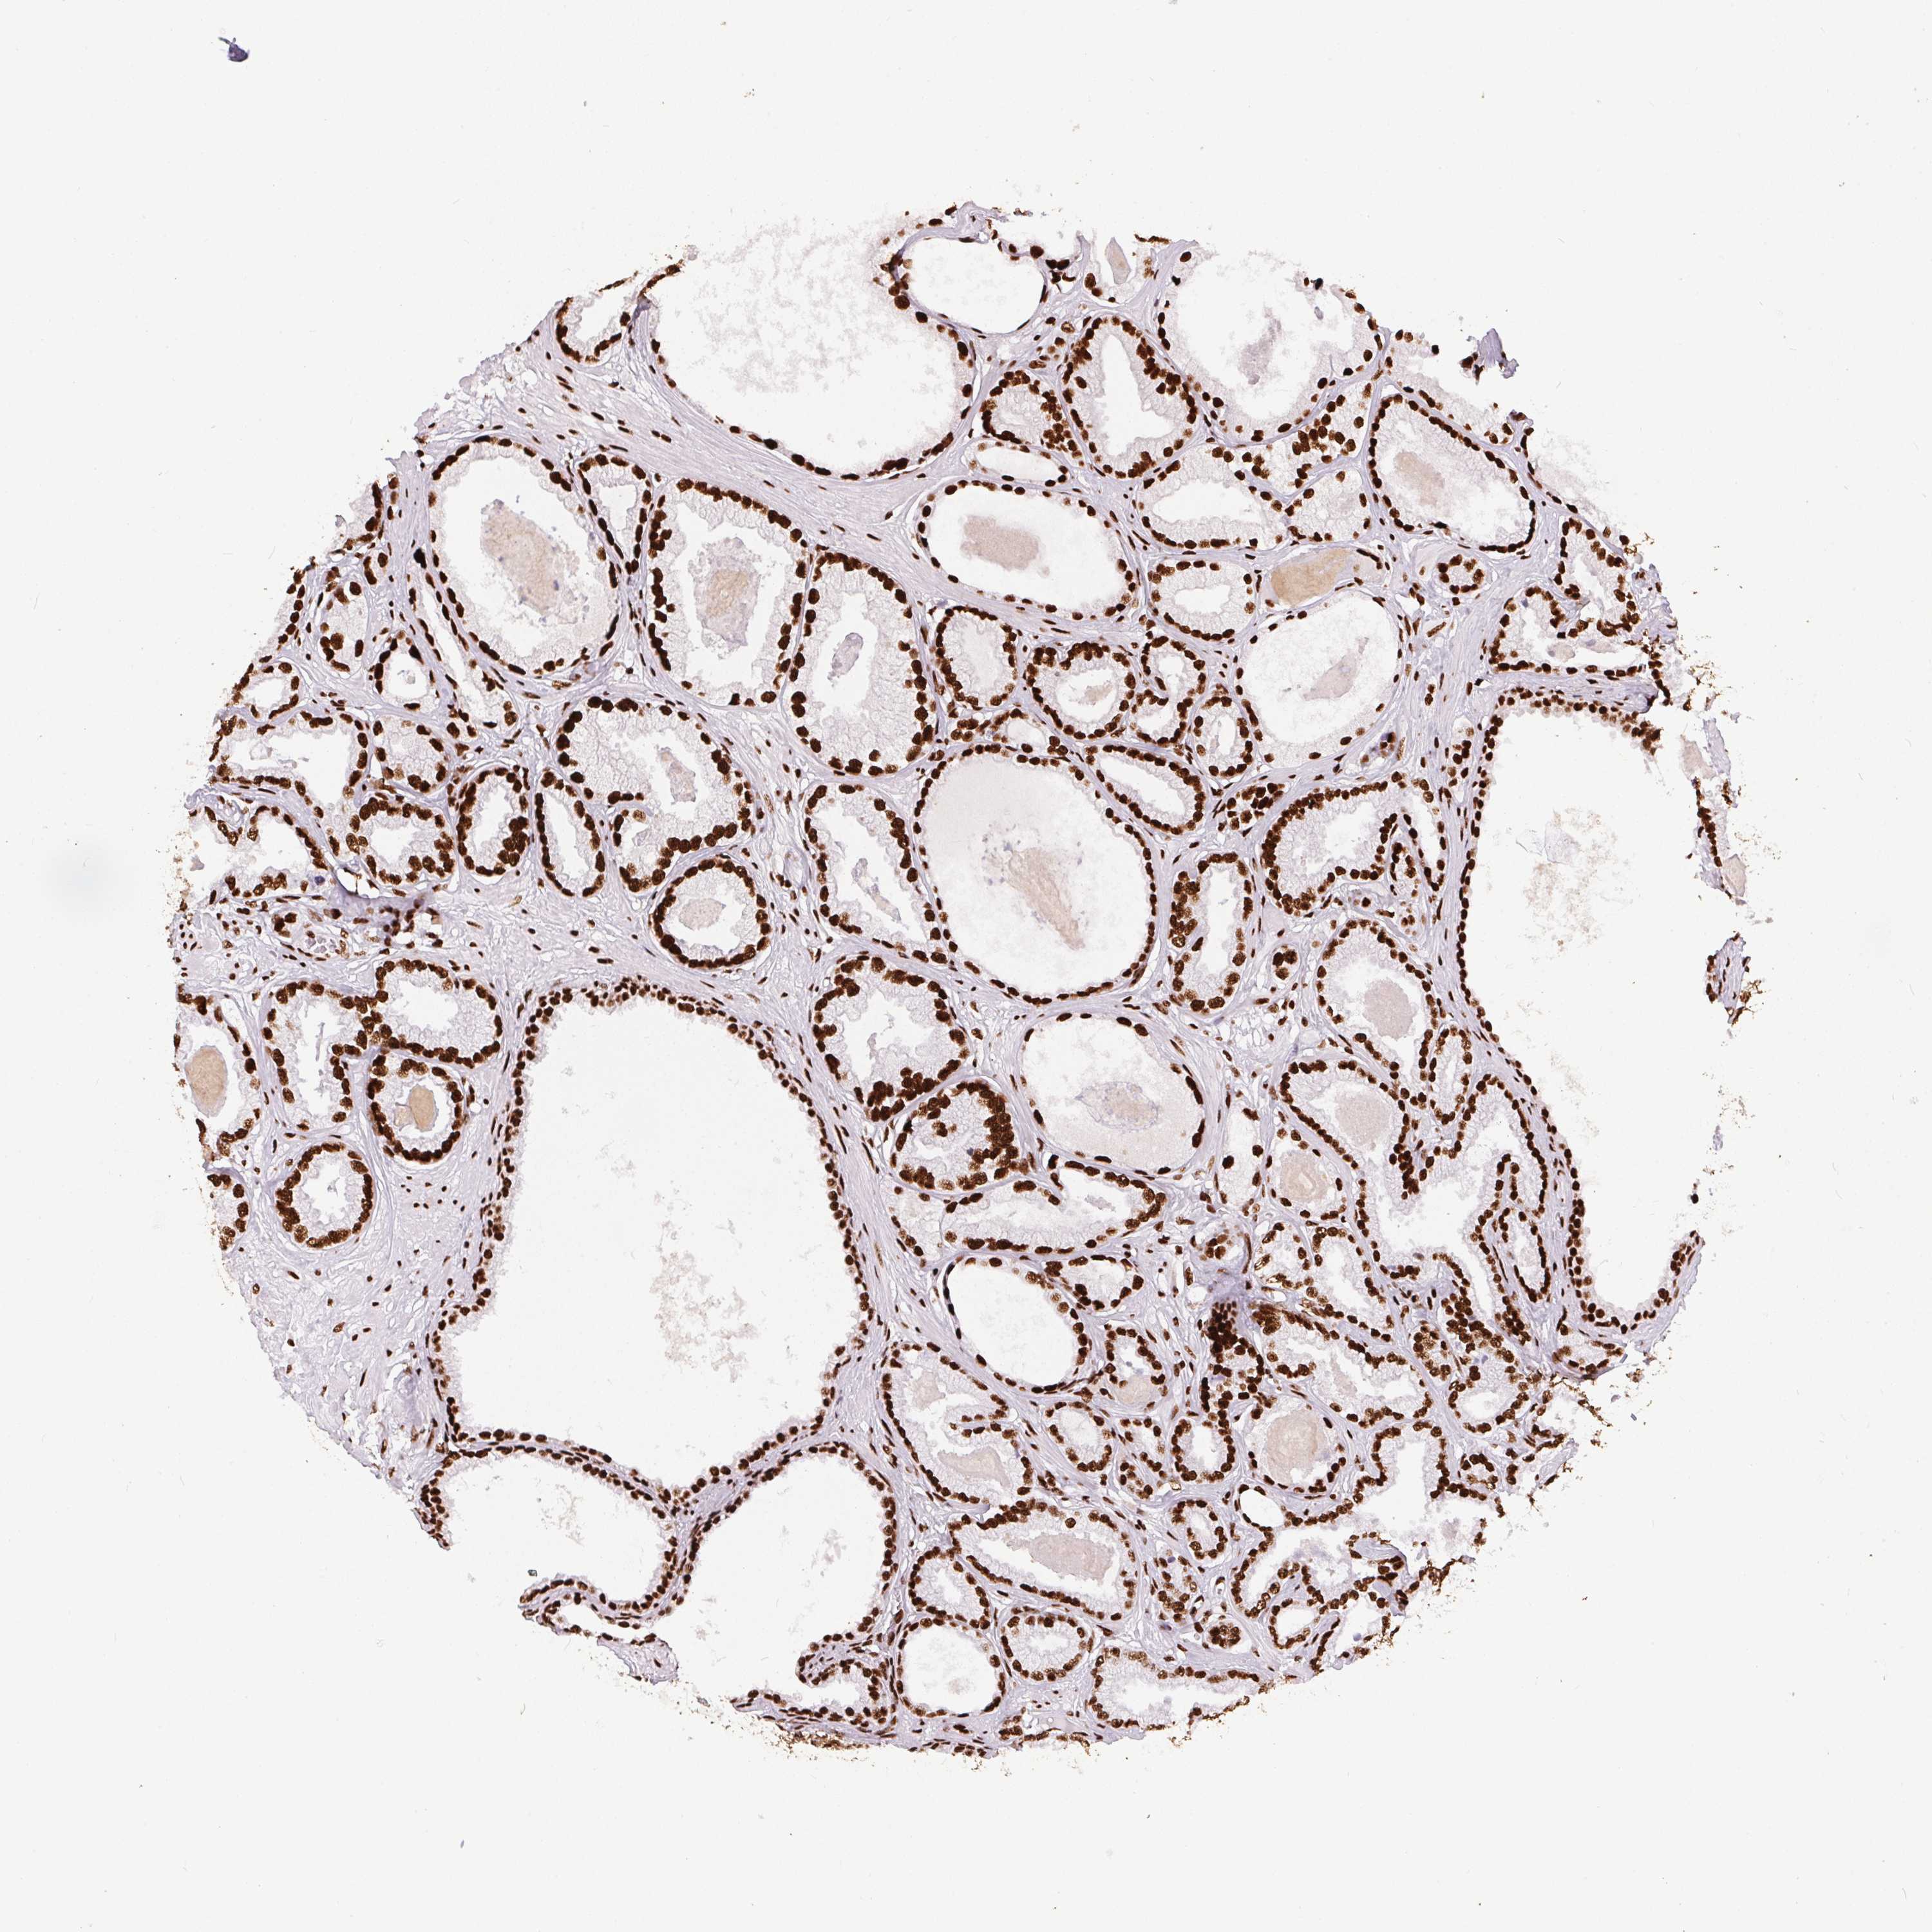

PROSTATE CANCER - Protein expressioni

A mouse-over function shows sample information and annotation data. Click on an image to view it in a full screen mode. Samples can be filtered based on level of antibody staining by selecting one or several of the following categories: high, medium, low and not detected. The assay and annotation is described here.

Note that samples used for immunohistochemistry by the Human Protein Atlas do not correspond to samples in the TCGA dataset.

Antibody stainingi

Antibody staining in the annotated cell types in the current human tissue is reported as not detected, low, medium, or high, based on conventional immunohistochemistry profiling in selected tissues. This score is based on the combination of the staining intensity and fraction of stained cells.

Each image is clickable and will lead to virtual microscopy that enables deeper exploration of all samples and also displays staining intensity scores, fraction scores and subcellular localization as well as patient and tissue information for each sample.

Antibody HPA062248

Staining

High

Medium

Low

Not detected

Intensity

Strong

Moderate

Weak

Negative

Quantity

>75%

75%-25%

<25%

None

Location

Nuclear

Cytoplasmic/membranous

Cytoplasmic/membranous,nuclear

Adenocarcinoma, High grade

Adenocarcinoma, NOS

Adenocarcinoma, Low grade